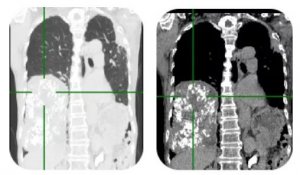

济宁市第一人民医院胸外科为七旬老人成功切除肺部巨大肿瘤

79岁的殷老太近半月来出现胸闷乏力,CT检查发现:老人右侧胸...